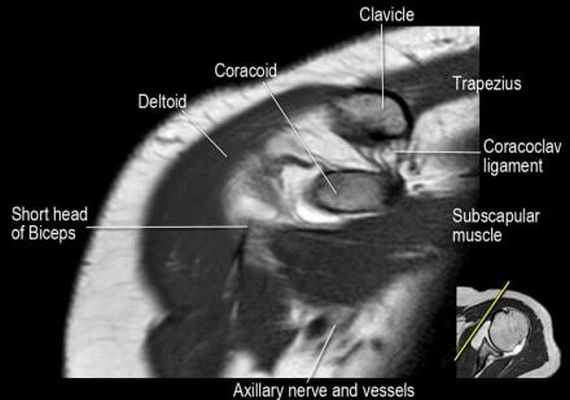

Нормальная корональная анатомия плечевого сустава и контрольный список

- обратите внимание на клюво-ключичную связку (coracoclavicular ligament) и короткую головку двуглавой мышцы (short head of the biceps).

- обратите внимание на клювоакромиальную связку (coracoacromial ligament).

- -

- обратите внимание на надлопаточный нерв и сосуды (suprascapular nerve and vessels)

- поищите импинджмент надостной мышцы за счет остеофитов в акромиально ключичном суставе или из-за утолщения клювовидноакромиальной связки.

- изучите верхний комплекс двуглавой мышцы и суставной губы, поищите подгубный карман илм SLAP-повреждение

- поищите скопление жидкости в подакромиальной сумке и повреждение сухожидия надостной мышцы